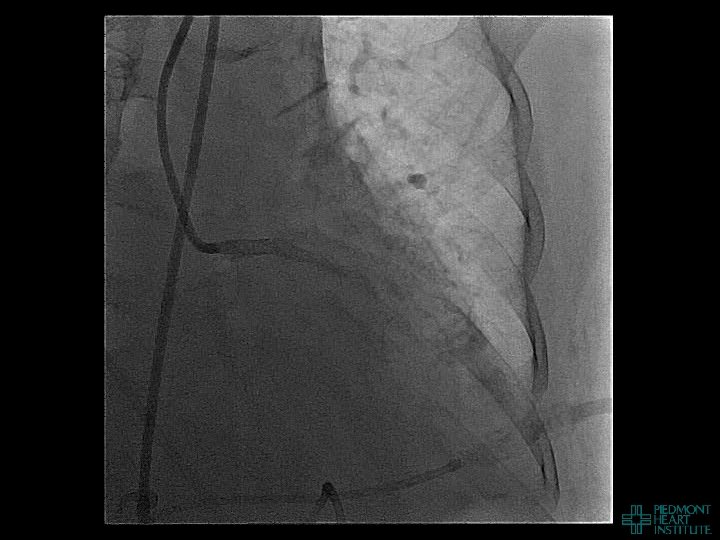

Case Example 2